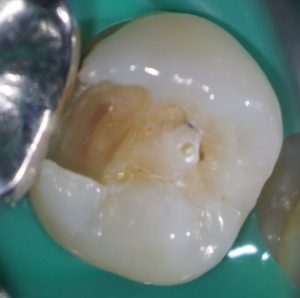

たとえば、この症例はいかがでしょう。

中心結節がある症例では、中心結節に歯髄が嵌入していることが知られています。

この症例を普通に治そうとするとインレーになりますよね。

しかし、通法の形成ではイスムスを形成しているときに露髄してしまうかもしれません。

私はこういった症例の治療をする場合、う蝕を取り除き、

露髄していないことを確認したうえで、コンポジットレジンで修復することがほとんどです。

これを自由診療で行っています。

患者さんは、歯髄を失わなくて済むので自由診療を選択したことをとても喜んでくれます。